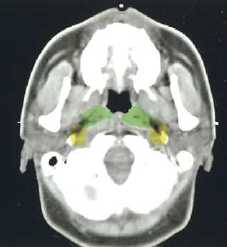

(a–l) Marked lymph nodes (LNs) with each LN group separated by color.

Light blue, submental LN (Ia);

dark blue, submandibular LN (Ib);

yellow, jugular LN (II, III, IV);

red, spinal accessory LN (V);

light green, retropharyngeal LN;

orange, parotid LN;

dark green, anterior jugular LN (VI);

pink, retroauricular/occiptal LN.